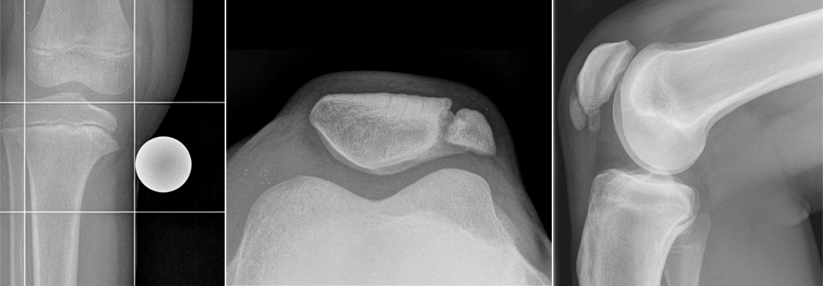

Die bisherigen Daten sprechen dafür, dass ein Krafttraining patellofemorale Schmerzen lindert. Unklar war jedoch, ob eher die Muskulatur von Knie oder Hüfte beübt werden sollte. Auf der Suche nach einer Antwort starteten dänische Wissenschaftler eine kontrollierte Studie.

Die Auswertung ergab eine Differenz von 7,6 Punkten für die gezielte Kräftigung des vierköpfigen Oberschenkelmuskels. Mit dem „Hüfttraining“ wurden 7,0 Punkte erreicht. Die erzielte Verbesserung war zwar in beiden Gruppen statistisch signifikant, vom Effekt her allerdings sehr klein. Zum Nachweis eines klinisch relevanten Nutzens hätten die Teilnehmer eine Veränderung um mindestens acht Punkte erreichen müssen.

Als sekundäre Zielgröße wurde der Knee Injury and Osteoarthritis Outcome Score (KOOS) erhoben mit den Subdomänen Schmerz, körperliche Funktion und kniebezogene Lebensqualität. Diesbezüglich war kein Unterschied zu erkennen.